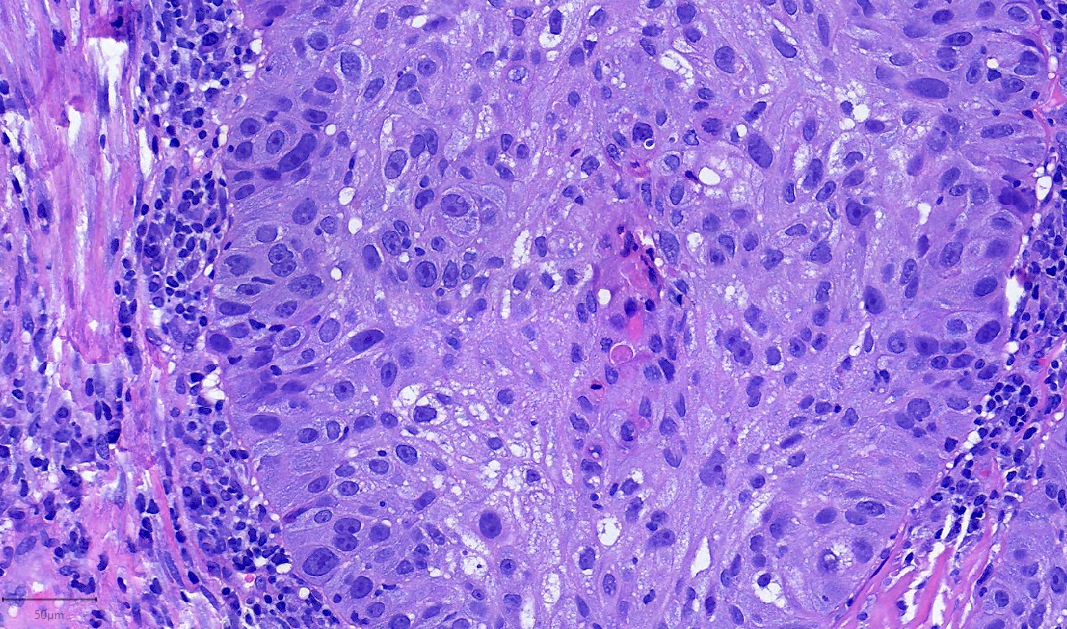

Pathology Outlines NUT carcinoma

From www.pathologyoutlines.com

Pathology Outlines NUT carcinoma Nut Lung Carcinoma Web nut carcinoma (nc) is a rare and aggressive subtype of squamous carcinoma characterized by genetic. Web nuclear protein of the testis carcinoma (nc), also known as nut. Web nut carcinoma of the thorax is a rare and very aggressive tumor, whose definition is based on the demonstration of a nuclear. Web nut carcinoma is a rare, highly aggressive cancer. Nut Lung Carcinoma.

Pathology Outlines NUT carcinoma Nut Lung Carcinoma Nut carcinoma (nc), also known as nut midline carcinoma, is a type of rare cancer that can grow. Web nut carcinoma is a rare, highly aggressive cancer that feature as the rearrangement of the nuclear protein in the. Web nut carcinoma, also called midline nut carcinoma, is an aggressive cancer that typically starts in the lungs or. Web nut carcinoma. Nut Lung Carcinoma.

Pathology Outlines NUT carcinoma Nut Lung Carcinoma Web nut carcinoma is a rare, highly aggressive cancer that feature as the rearrangement of the nuclear protein in the. It’s the most aggressive type of squamous cell carcinoma. Web nut carcinoma, also called midline nut carcinoma, is an aggressive cancer that typically starts in the lungs or. Web what is nut carcinoma? Nut carcinoma (nc), also known as nut. Nut Lung Carcinoma.

Pathology Outlines NUT carcinoma Nut Lung Carcinoma Web nuclear protein of the testis carcinoma (nc), also known as nut. Web what is nut carcinoma? Web nut carcinoma is a rare, highly aggressive cancer that feature as the rearrangement of the nuclear protein in the. It’s the most aggressive type of squamous cell carcinoma. Web nut carcinoma (nc) is a rare and aggressive subtype of squamous carcinoma characterized. Nut Lung Carcinoma.

Pathology Outlines NUT carcinoma Nut Lung Carcinoma Web nut carcinoma (nc) is a rare and aggressive subtype of squamous carcinoma characterized by genetic. Nut carcinoma (nc), also known as nut midline carcinoma, is a type of rare cancer that can grow. Web nut carcinoma is a rare, highly aggressive cancer that feature as the rearrangement of the nuclear protein in the. Web nut carcinoma of the thorax. Nut Lung Carcinoma.